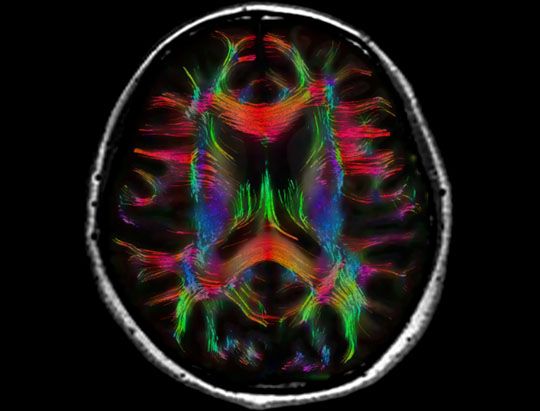

256 Direction DTI Fiber Tracking